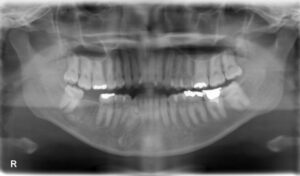

下顎大臼歯1本欠損症例

BEFORE AFTER 30歳女性/下顎1本欠損/インプラント埋込手術 【治療内容】 右下第二大臼歯が欠損した状態でご…